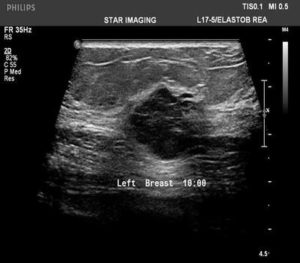

39yr old lady with history of lump in the left breast UIQ, No previous imaging done. No positive family history for CA Breast/Ovary. Pre-Menopausal Status.

Mammography- Fairly well circumscribed predominantly sold lesion in the left breast UIQ with partially obscured margins. No spiculations. No associated microcalcifications noted. Sonography: Well defined hypoechoiec lesion with smooth margins.

Low-grade Mucinous Carcinoma ER?PR- +ve HER-2 NEU -VE